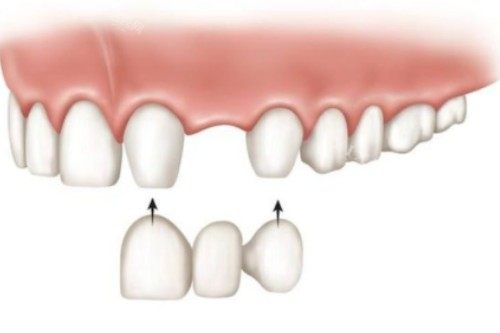

3. 全瓷牙:美学与功能的平衡

价格区间:880元-6800元/颗

代表产品:

国产经济型:武汉品德口腔的二氧化锆全瓷牙880元/颗

进口品质型:德派口腔的德国威兰德全瓷牙3600元/颗

奢望定制型:武大口腔的3M LAVA全瓷牙6800元/颗

适用人群:前牙美学修复、对金属过敏者。

优势:透光性强,牙龈无黑线;劣势:脆性较高,不适合后牙大范围缺损。

4. 烤瓷牙:传统修复的性价比方案

价格区间:380元-2500元/颗

代表材质:

普通金属:武汉品德口腔的钴铬合金烤瓷牙590元/颗

贵金属:纯钛烤瓷牙2500元/颗(生物相容性更佳)

超低价选项:部分机构促销价380元/颗(需确认材质靠谱性)

适用人群:后牙修复、预算敏感型用户。

优势:强度高,价格适中;劣势:长期使用可能导致牙龈染色。